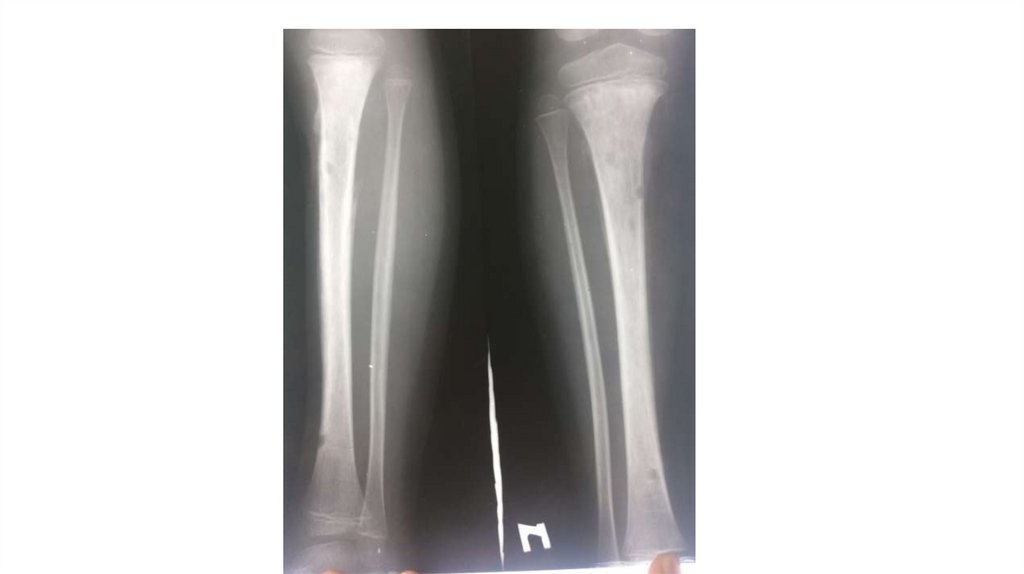

Воспалительные заболевания опорнодвигательного аппарата

заболевания опорнодвигательного аппарата»